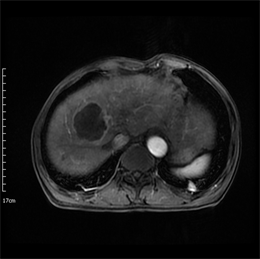

Figure 1. Axial MRI images of HCC patient before TACE treatment. (a) T1-weighted unenhanced image shows a hypointensive lesion in right lobe of liver. (b) Arterial phase contrast-enhanced image shows a heterogeneous enhanceed lesion. (c) ADC map. (d) Dslow map. (e) Dfast map. (f) f map.